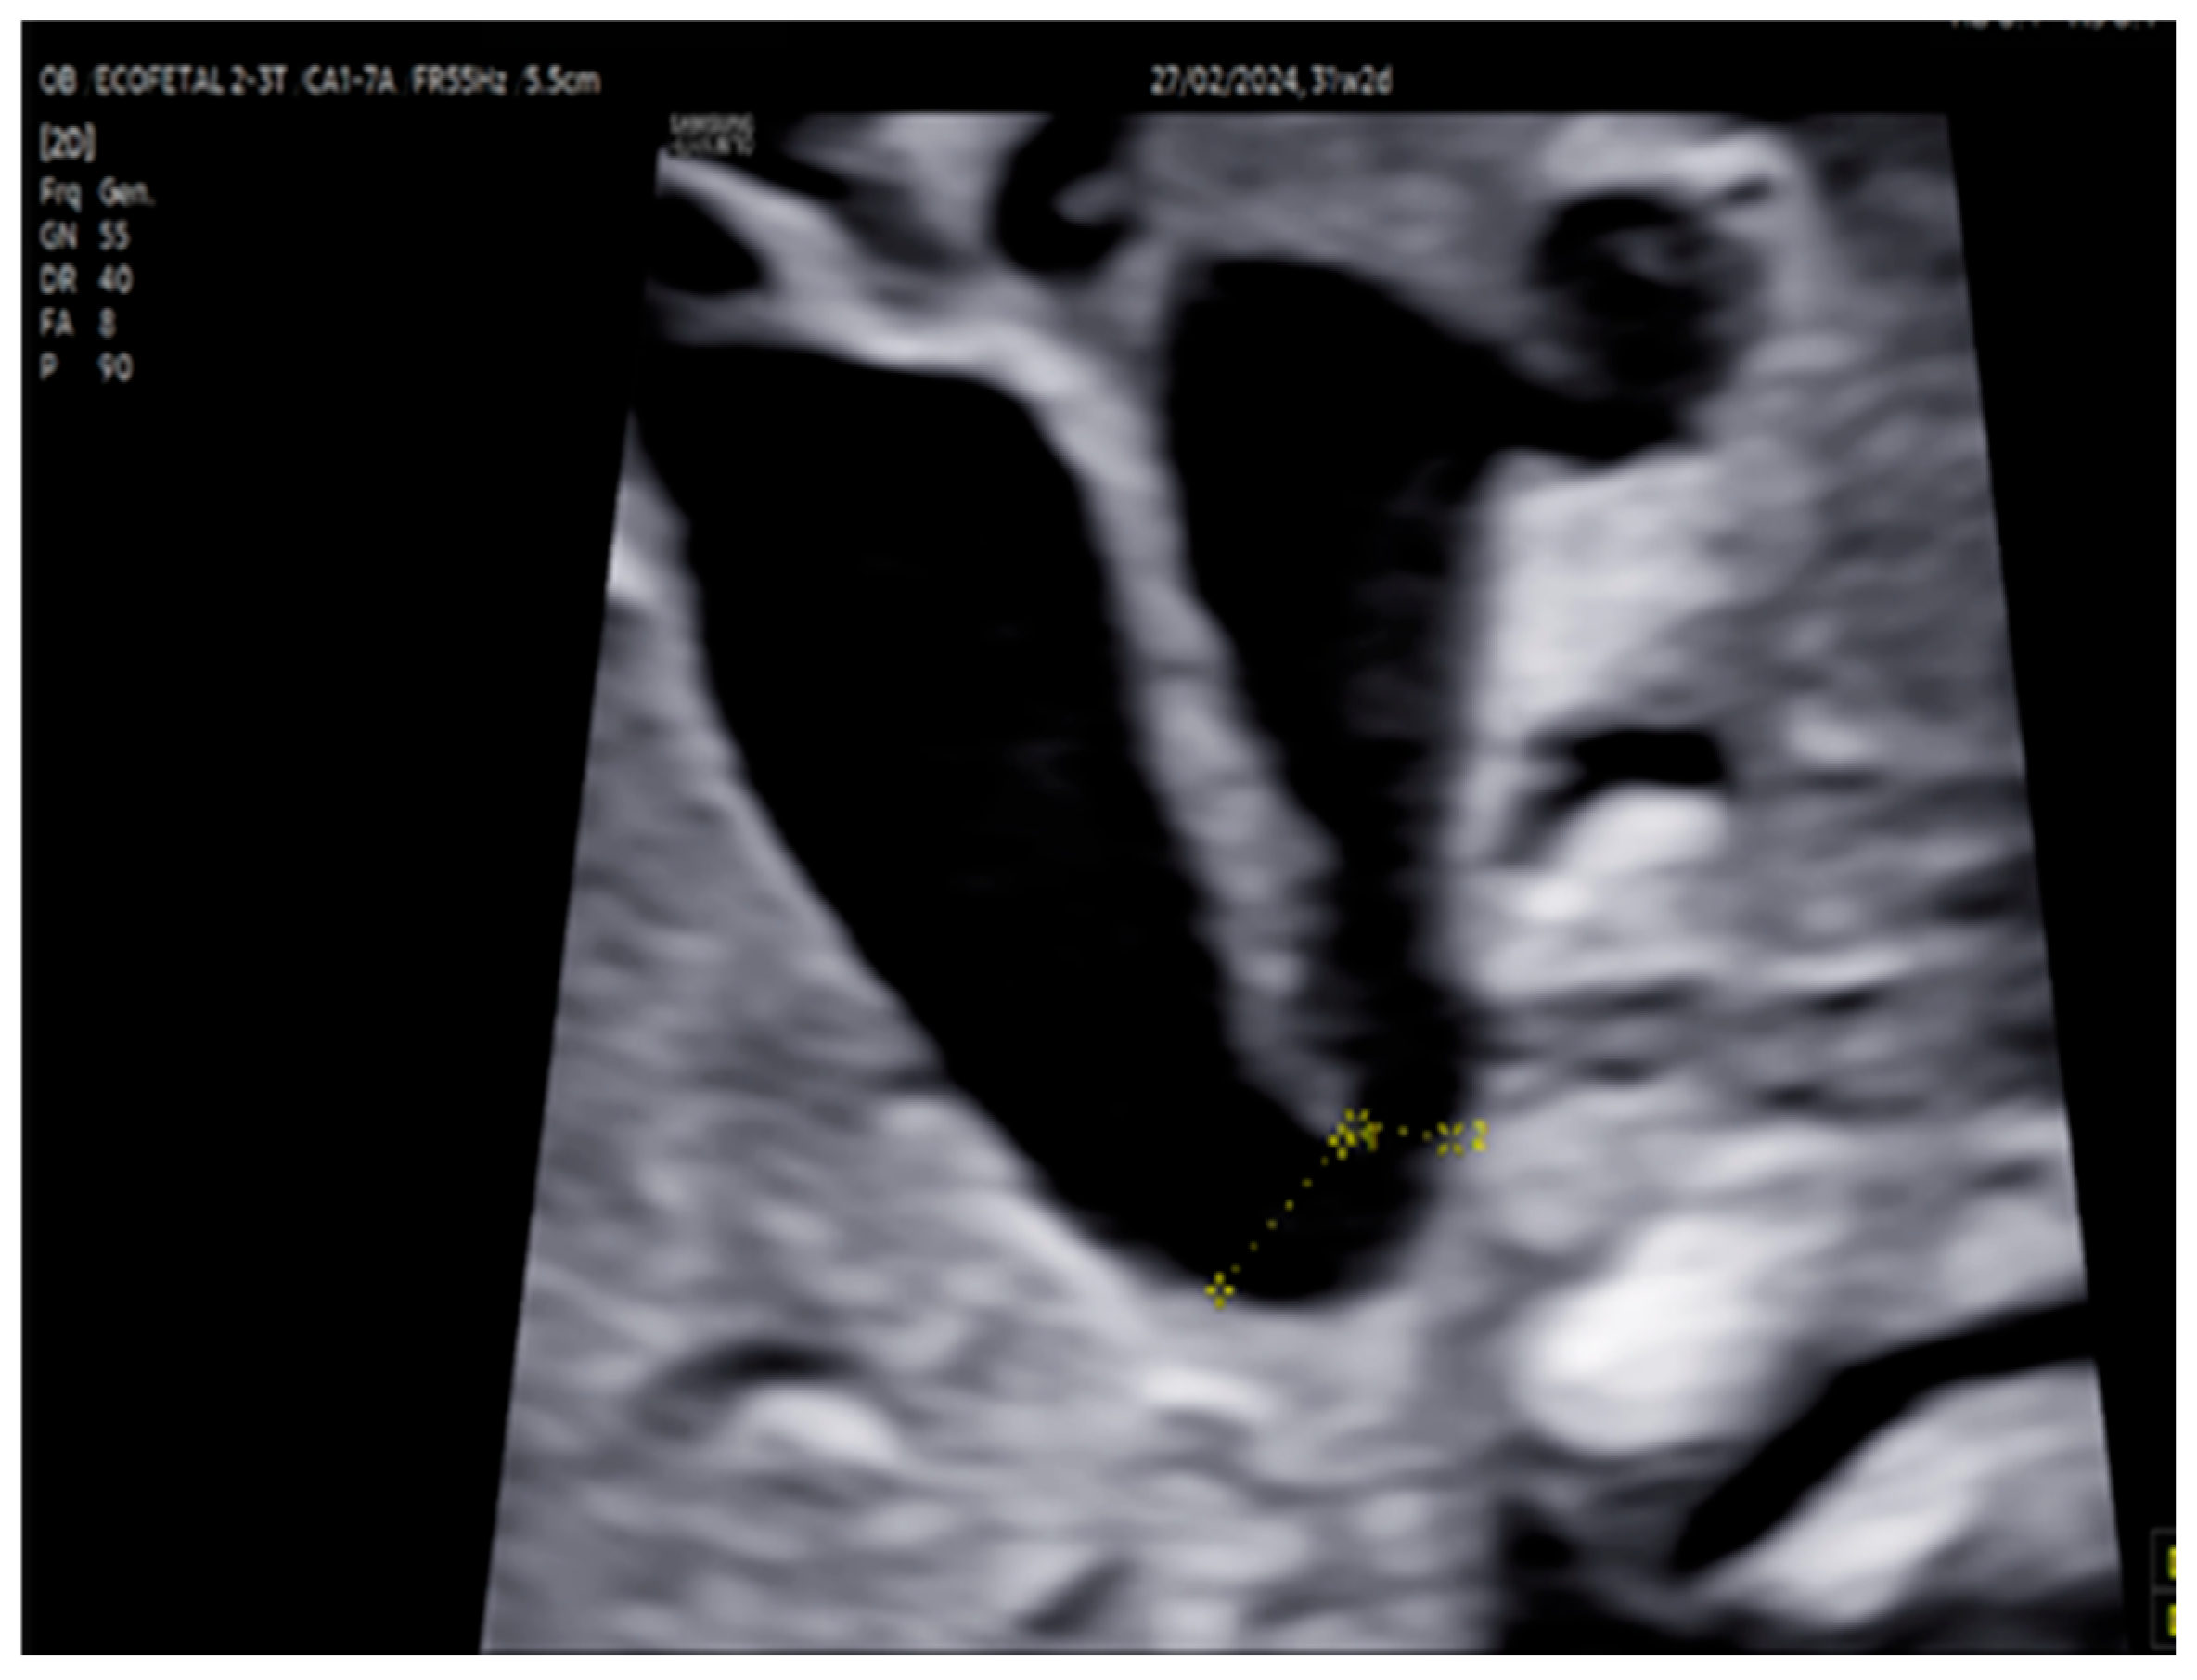

| 31 + 2 | Post-IVIG peak response | 70 | SF: 59% (LV), 52% (RV); marked biventricular improvement | Aortic isthmus 3 mm (Z-score –1.65) |

| 33 + 0 | Second IVIG cycle | 68 | Stable function maintained | Repeated full protocol; no complications |